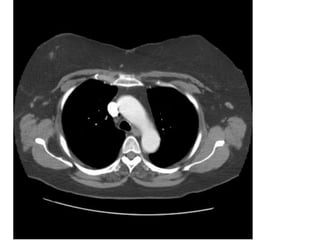

• Chụp CT ngực không cản quang

• Chụp CT ngực có cản quang

XEM HÌNH KHÔNG CHÍCH CHẤT TƯƠNG PHẢN (CE-) TRƯỚC

RỒI MỚI ĐẾN HÌNH CÓ CHÍCH CHẤT TƯƠNG PHẢN (CE+)